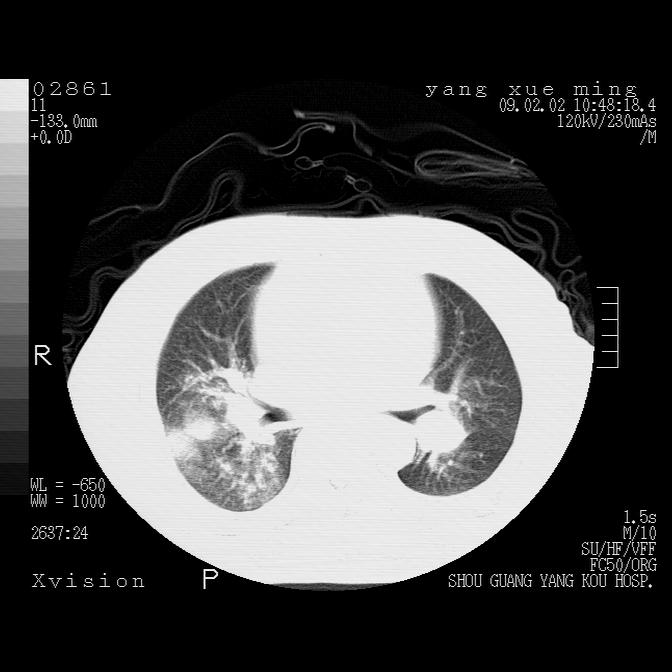

以下是引用zbp537在2009-2-3 19:08:00的发言:[br]我诊断为肺泡性肺水肿。[br]诊断依据:[br]1、心影普遍增大,肺血管增粗,并见絮状高密度影,肺门改变显著。[br]2、临床上表现胸闷咳嗽,无发烧,不是一个典型的肺部感染的病史。

以下是引用lkc8963在2009-2-3 20:11:00的发言:[br]1)右上肺陈旧病灶。2)右下肺团块及团片影,影像表现符合感染。3)左心增大,左冠脉钙化,符合冠心病。4)双侧肺门扩大,以左侧为著,肺动脉干略粗,左上肺局限性气肿,为谨慎起见,需除肿瘤,建议增强。

以下是引用lkc8963在2009-2-3 20:11:00的发言:[br]1)右上肺陈旧病灶.2)右下肺团块及团片影,影像表现符合感染.3)左心增大,左冠脉钙化,符合冠心病.4)双侧肺门扩大以左侧为著,肺动脉干略粗,左上肺局限性气肿,为谨慎起见,需除肿瘤,建议增强.